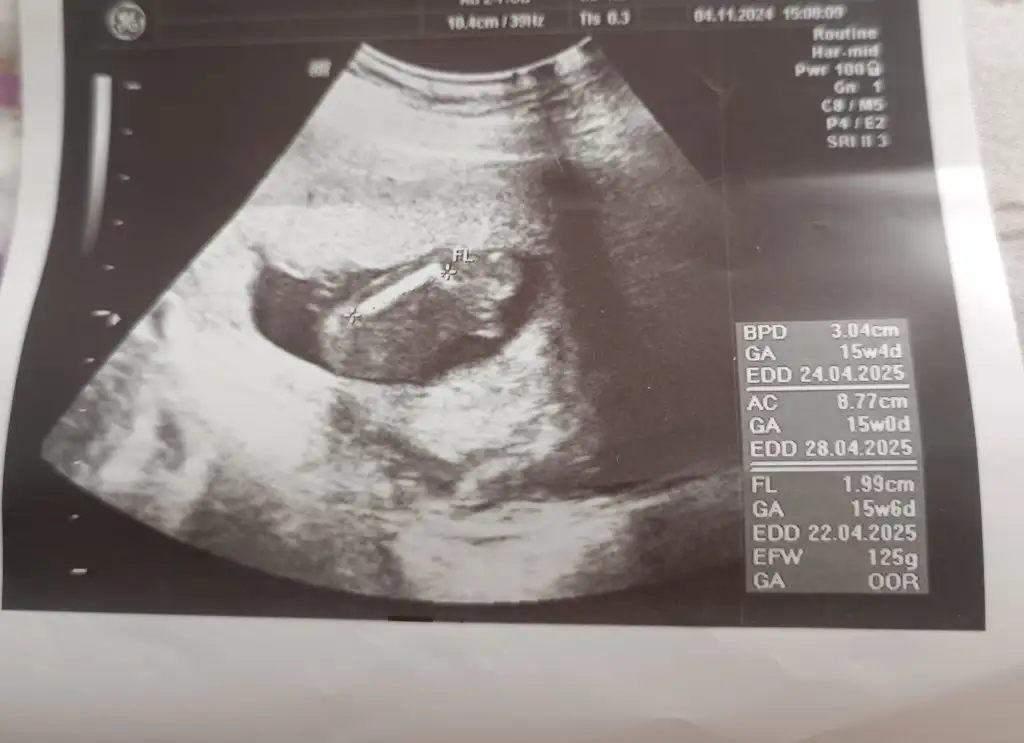

• IMG_20241105_134832.webp

IMG_20241105_134832.webp

23,9 KB · Görüntüleme: 92

• IMG_20241105_134810.webp

IMG_20241105_134810.webp

20 KB · Görüntüleme: 77

• IMG_20241105_134740.webp

IMG_20241105_134740.webp

23,2 KB · Görüntüleme: 74

Tahmin eder misiniz